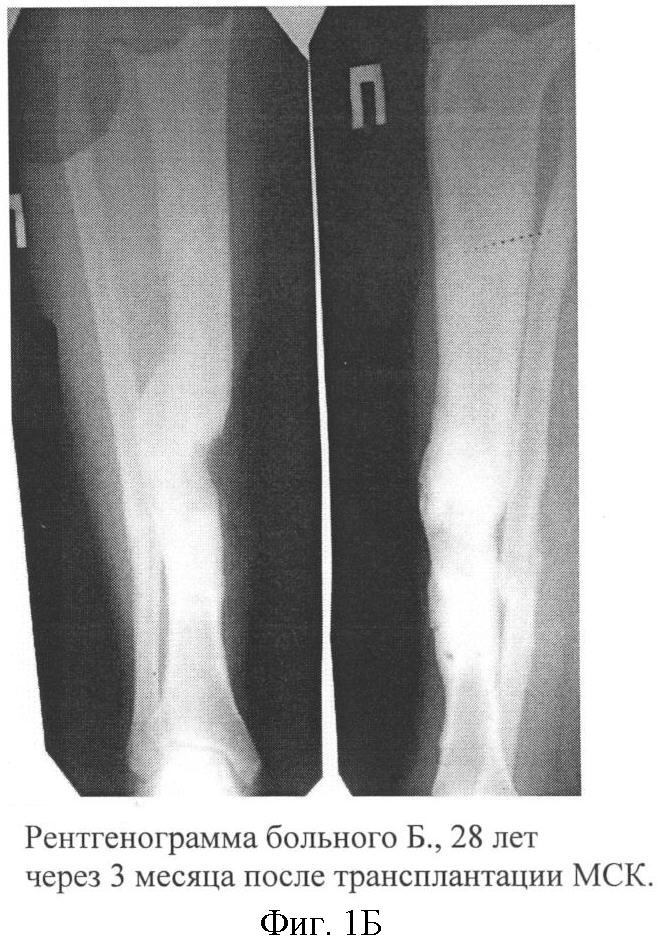

Больной Б., 28 лет, находился на лечении в хирургическом отделении МУЗГКБ 2 с диагнозом: «Хронический посттравматический остеомиелит левой большеберцовой кости в средней трети, свищевая форма; ложный сустав с дефектом костной ткани в средней трети левой большеберцовой кости». Из анамнеза: травма 3 года назад – открытый оскольчатый перелом костей левой голени в средней трети. При поступлении выполнен металлоостеосинтез. Послеоперационный период осложнился развитием остеомиелита. Неоднократно проводились санирующие операции и реостеосинтез, костная аутопластика без эффекта. У больного сохранялся свищ с гнойным отделяемым, больной передвигался с использованием костылей без опоры не конечность. Рентгенологически признаки ложного сустава (фиг.1А). 20.09.07 г. выполнена операция – иссечение свища, некрсеквестрэктомия, дренирование остеомиелитического очага. Иммобилизация гипсовой повязкой. После купирования признаков острого воспалительного процесса выполнены последовательные трансплантации МНК и МСК по описанной схеме. Послеоперационная рана зажила первичным натяжением, признаков воспалительного процесса за период наблюдения не было. Через 3 месяца после имплантации, клинически перелом консолидировался, гипсовая повязка снята. На контрольной рентгенограмме: выраженная костная мозоль по внутренней поверхности средней трети левой большеберцовой кости. Периостальная реакция не отмечается (фиг.1Б). В течение 6 месяцев признаков обострения остеомиелита не было. Больной ходит, не используя дополнительные средства опоры.